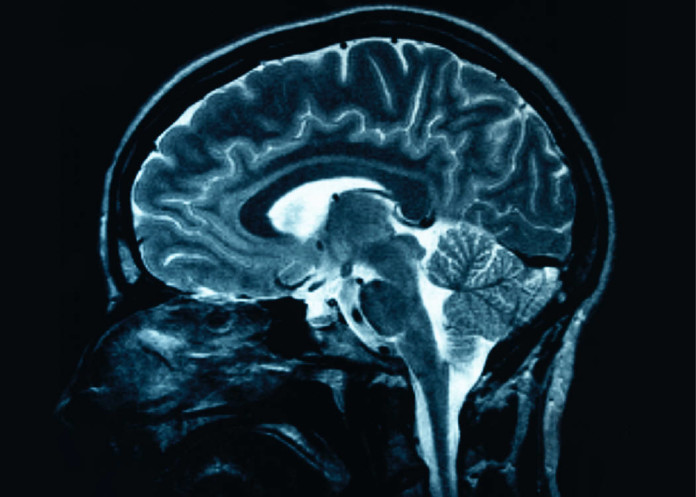

Un sistema no reconocido previamente que drena los desechos desde el cerebro a un ritmo muy rápido ha sido descubierto por neurocientíficos de la Universidad de Rochester Medical Center. Los hallazgos fueron publicados en el 15 de agosto en Science Translational Medicine.

El sistema altamente organizado actúa como una serie de tubos que aprovecha los vasos sanguíneos del cerebro, una especie de un sistema de tuberías que parece servir la misma función en el cerebro como el sistema linfático hace en el resto del cuerpo – para drenar los productos de desecho.

El equipo hizo los descubrimientos en ratones, cuyos cerebros son muy similares al cerebro humano. Los científicos han sabido que el líquido cefalorraquídeo o CSF juega un papel importante la limpieza del tejido cerebral, llevando para fuera los productos de desecho y llevando nutrientes al tejido cerebral a través de un proceso conocido como difusión.

El sistema glifatico es como una capa de tubería que rodea a los buques existentes sanguíneos del cerebro. El equipo encontró que las células gliales llamadas astrocitos utilizan las proyecciones conocidas como «patas de finales» para formar una red de conductos en torno a las afueras de las arterias y venas dentro del cerebro, similar a la forma de un dosel de ramas de los árboles a lo largo de una calle muy arbolada podría crear una especie de canal por encima de la calzada. Esos pies finales se llenan con estructuras conocidas como canales de agua o acuaporinas, que se mueven LCR a través del cerebro.

El equipo encontró que el CSF se bombea en el cerebro a lo largo de los canales que rodean las arterias, luego se lava a través del tejido cerebral antes de recoger en los canales alrededor de las venas y el drenaje del cerebro.